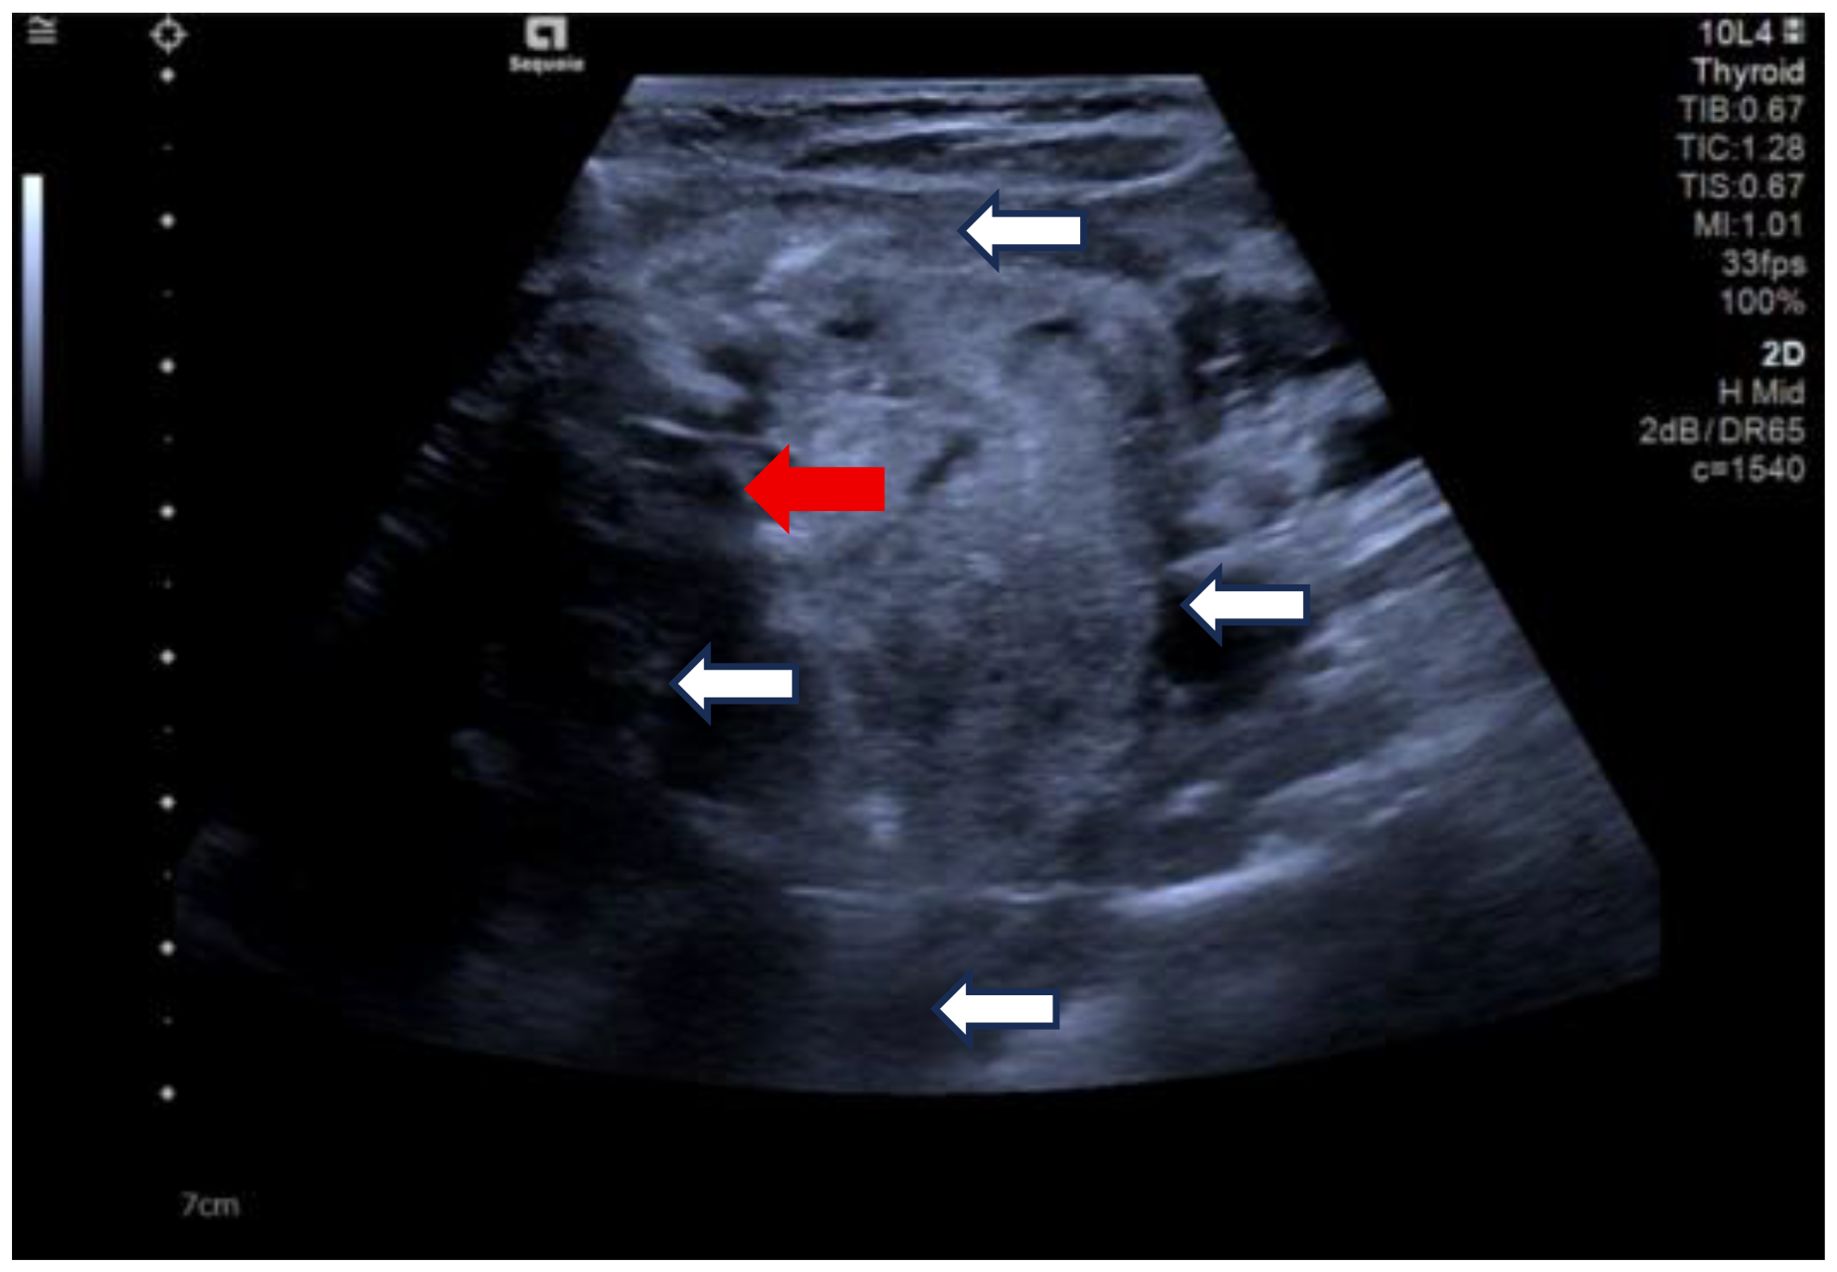

Due to her prior thyroid surgery and strong preference to avoid further surgery, the patient strongly requested a non-surgical treatment approach. After a thorough discussion, we performed an ultrasound-guided fine-needle aspiration biopsy (FNAB), which yielded a Bethesda III lesion and negative for BRAF gene. Based on the clinical and imaging examination, we opted for ultrasound-guided radiofrequency ablation (RFA) as the treatment modality. Before the ablation treatment, contrast-enhanced ultrasound (CEUS) showed that the nodule’s enhancement pattern was similar to the surrounding thyroid parenchyma, with synchronous enhancement and regression. After disinfecting the neck and spreading a towel, local infiltration anesthesia was applied, followed by injection of 30 ml of saline into the anterior and posterior spaces of the left thyroid and the paratracheal space under ultrasound guidance and real-time monitoring, and an isolation zone was formed around the giant nodule in the left lobe (Figure 3), and the thickness of the zone was ≥5 mm. Once an adequate isolation zone was established, the RFA needle (needle type: using an internally cooled 18G electrode, 10cm in length, and with a 10mm active tip size, powered by the RF generator (AJ-500A, Angel Medical))was inserted near the posterior aspect of the mass, and ablation commenced. The procedure was performed in a stepwise manner, retreating and adjusting the needle path to ensure complete treatment from the deep to the superficial portions of the nodule. The procedure lasted 20 minutes and 53 seconds at a power of 60W. While strong echogenicity on 2D ultrasound indicated near-complete ablation, residual contrast enhancement on CEUS suggested a small untreated area. Additional ablation was performed until both 2D ultrasound and CEUS confirmed complete lesion necrosis. The total ablation time was 25 minutes and 20 seconds. Throughout the procedure, the patient remained conscious and communicative, allowing continuous assessment of her vocal function. Vital signs, oxygen saturation, and ECG were monitored to ensure procedural safety. The patient experienced only mild neck discomfort and no complications such as bleeding or dyspnea. One month after the procedure, ultrasound of the patient’s follow-up showed a hypoechoic region at the ablation site with “black hole” changes on CEUS, indicating effective necrosis (Figure 4). Postoperative thyroid function remained normal, vocal function was preserved, and the patient expressed high satisfaction with the cosmetic outcome, especially the absence of a surgical scar.

Figure 3. Clockwise from top, the anterior thyroid space, the lateral thyroid space, the posterior thyroid space and the paratracheal space are shown. (white arrows). Ablation needle position. (red arrow).